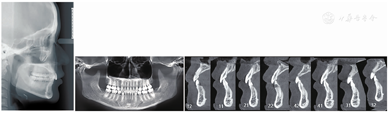

病例矫治时间约48个月,共佩戴上下颌118副矫治器。该病例上下颌后牙作为支抗牙,前牙设计了整体内收关闭拔牙间隙并压低至"切对切"。矫治结束时,全口牙齿排列整齐,磨牙近移,前牙内收关闭拔牙间隙,上、下前牙直立,唇倾度基本正常,覆

覆盖关系基本正常。磨牙维持中性关系,咬合关系良好(图12)。软组织侧貌及上、下唇突度改善(图12)。双侧颞下颌关节区未触及压痛,未闻及关节弹响及杂音。

像矫治后曲面断层片及侧位片显示,牙槽骨水平与术前基本一致,牙根平行度较好,牙根及牙槽骨未见明显吸收。双侧颞下颌关节形态和骨质未见明显改变(图13)。CBCT显示上、下前牙牙根及牙槽骨未见明显吸收(图2)。矫治前后侧位片重叠显示:患者上、下前牙各内收约5.0 mm和6.8 mm,上下后牙近中向移动,上下唇软组织各内收约2.7 mm和4.4 mm,上下唇突度改善(图14)。